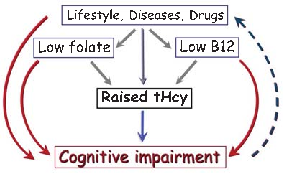

Brain imaging studies demonstrate that elevated homocysteine is associated with accelerated rates of brain atrophy, particularly in medial temporal lobe structures critical for memory. B-vitamin treatment appears to slow this atrophy in individuals with elevated baseline homocysteine.

Homocysteine and Dementia: An International Consensus Statement.

A causal model illustrates how elevated plasma homocysteine may contribute to dementia through multiple pathways, interacting with other risk factors such as age, hypercholesterolemia, and genetic predisposition. No single factor is sufficient alone; rather, combinations of component causes drive disease.

Homocysteine and Dementia: An International Consensus Statement.

Meta-analyses of cohort studies consistently indicate that elevated homocysteine is associated with approximately doubled risk of Alzheimer's disease. The strength of this association persists after adjustment for common confounders including age, sex, and education.

Homocysteine and Dementia: An International Consensus Statement.